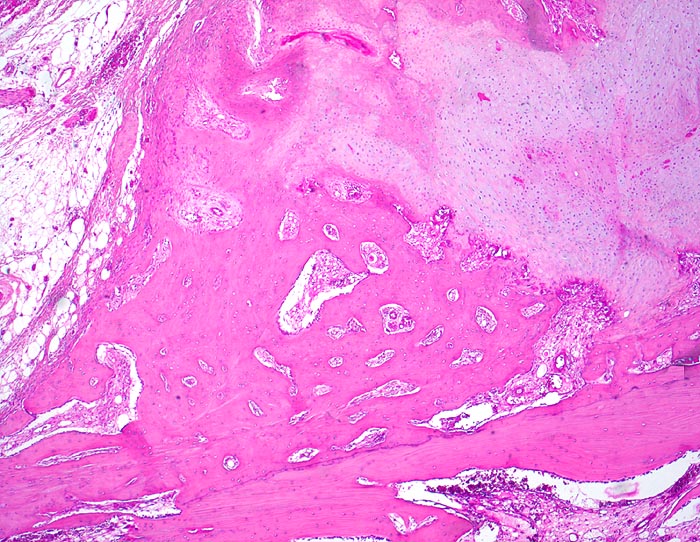

Morphologische Merkmale:

• Verschiebung der Bruchstücke gegeneinander.

• Über dem Frakturspalt senkrecht auf die Frakturlinie ausgerichtete Faserknochenbälkchen mit Osteoblastensaum und ausgedehnte Bezirke von neugebildetem Knorpel.

• Devitalisierter ortsständiger Knochen mit leeren Osteozytenhöhlen angrenzend an den Frakturspalt.

• Knochenmark zu beiden Seiten der Frakturlinie mit Markfibrose.

• Fibrinablagerung und Knorpelneubildung im Frakturspalt.

• Enchondrale Ossifiktation des neugebildeten Knorpels.

• Auch entfernt von der Bruchlinie Neubildung von Knochenbälkchen im Markraum.